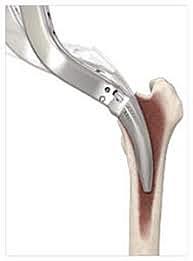

• Moore y Reyman

Moore y Reyman

diseñaron una nueva endoprótesis femoral de vitalio, que se fijaba intramedularmente en la diáfisis sin necesidad de emplear cemento

aordaje de Moore por vía posterior

Musculos: fibras del glúteo mayor y se seccionan los músculos gemelos y obturador interno